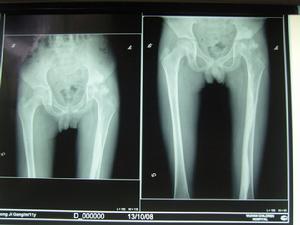

在長管狀骨皮質,呈連續或斷續的硬化骨條或斑塊,從近側向遠側伸延,多局限於一側骨皮質,亦可包繞整個骨皮質。骨表面高低不平,宛如熔化而滴流之蠟油。密度極高如象牙骨樣。增生骨周圍骨結構正常,增生過多時髓腔變窄。骨松質內亦可見不規則線狀、斑塊狀骨質增生。早期,骨的近關節部分不受累及,最終能伸入骨骺及跨越關節侵及另一骨幹。短管骨與骨骺的病變相似,表現為骨內有斑點狀或條紋狀緻密影,不易引起輪廓改變,關節多不受影響,即使關節兩端骨質發生明顯新骨堆積,關節面仍保持光滑,此乃本症特點之一。附近軟組織中常有骨質沉積。